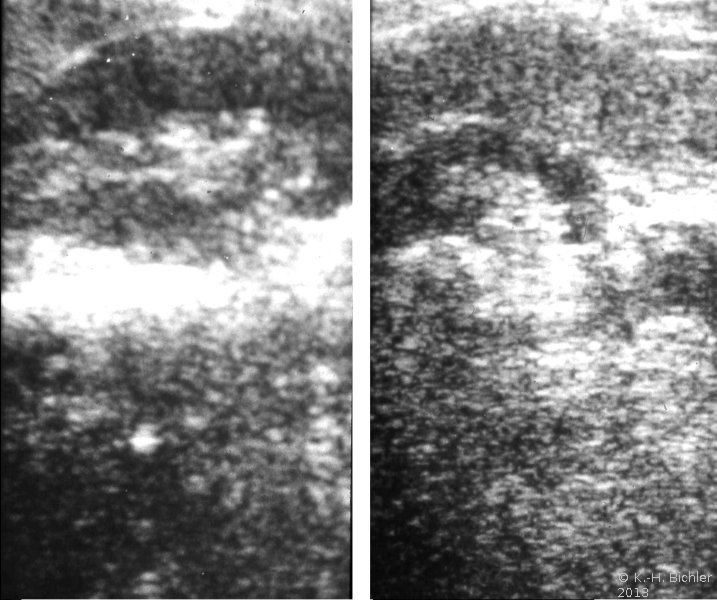

Neben der Anamnese, körperlicher Untersuchung, Messung des Blutdruckes sowie der Laboruntersuchungen: Urinstatus, Serumkreatinin und -Elektroylte ist die Sonographie zur Feststellung einer einseitig kleinen Niere zielführend (Abbildung 10a). Zur Diagnostik zählt fernerhin die NFZG (Abbildung 10b) bzw. Computertomographie.

Die Abbildungen zeigen die Anwendung von Sonographie und Miktionszysturethrogramm bei einer kleinen stummen Niere (Abbildung 13, 14).